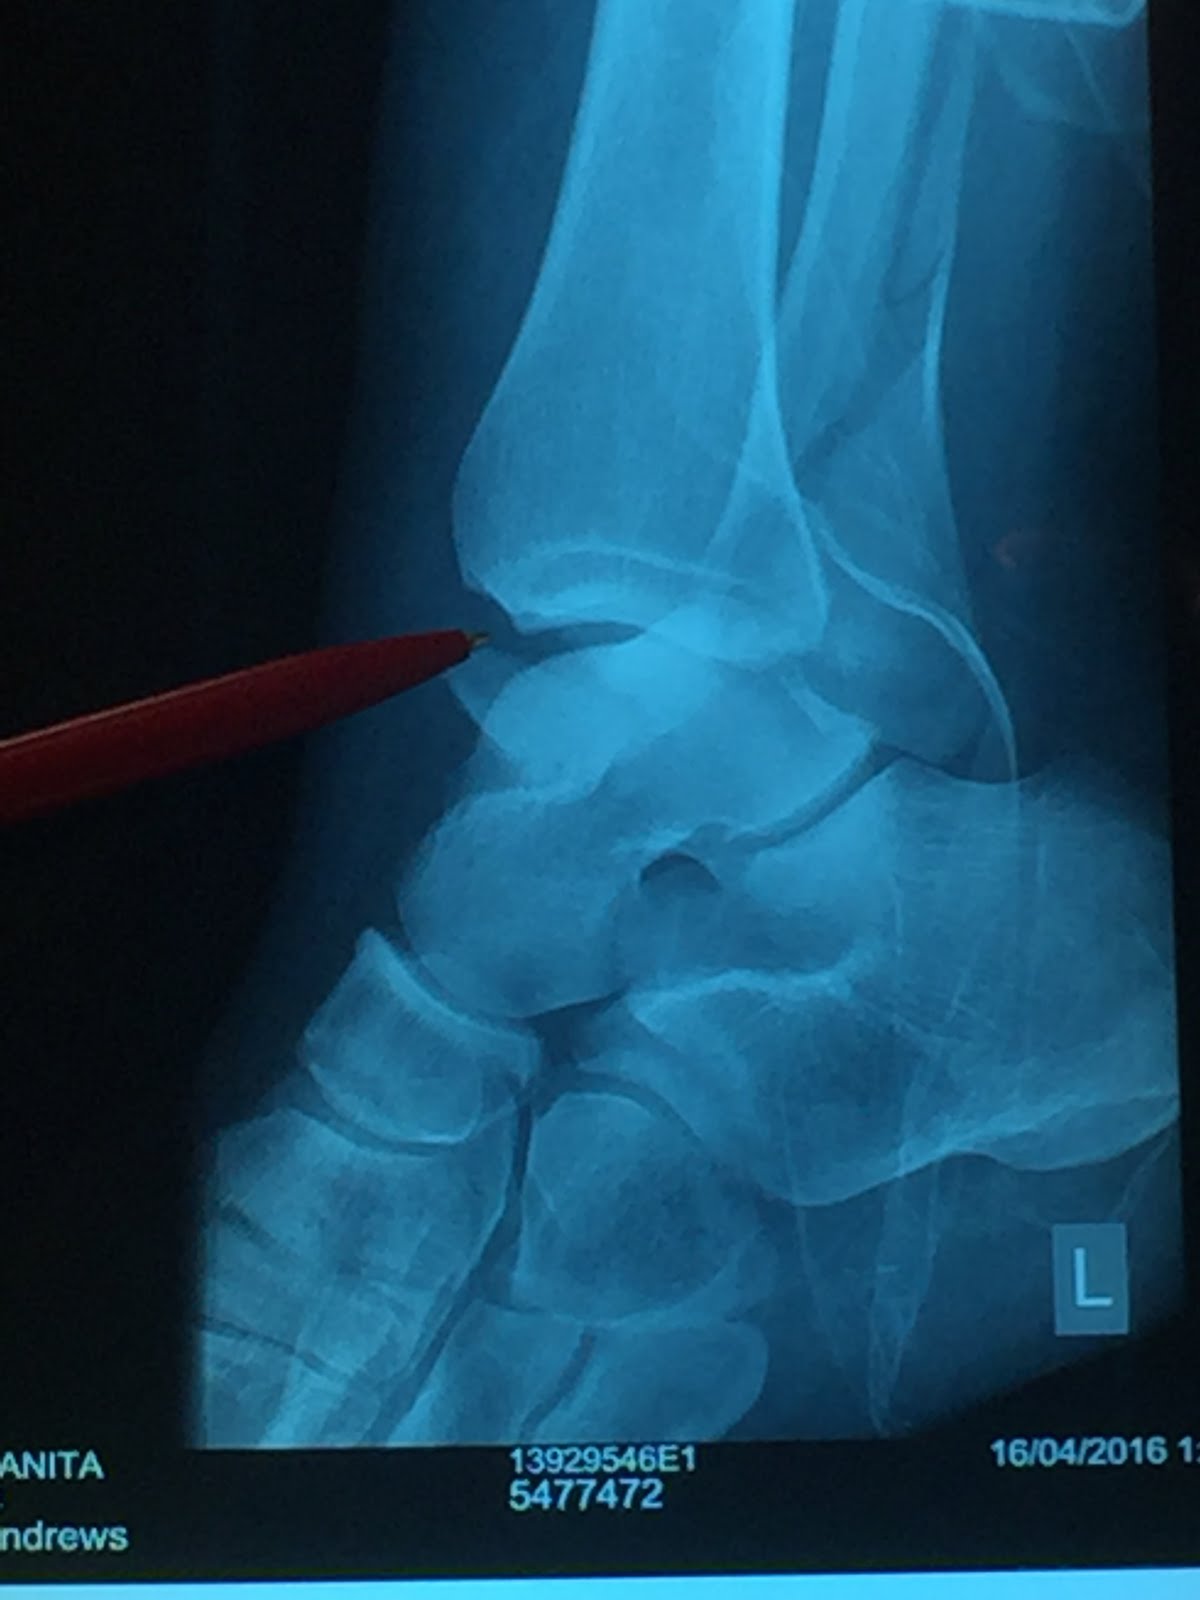

So, foot first to stop the lift doors closing, I was wheeled back. I was positive at this point my ankle was dislocated, because I figured that was what they saw on the X-ray. Pop it back in and still be home for dinner. Yay! Then the Doctor came in, put one Xray on the light box and went "yup there's the break in the fibula" (oh god), put up the second X-ray "there's another break" (pardon?), put up the third X-ray and said "there's a dislocation" (are you kidding me?"). I can't think if they told me then about the torn ligaments and things I was too busy internally freaking out. I still remember at this point thinking - "oh well, cast on and home!".

| Break Number 1 |

| Break Number 2 |